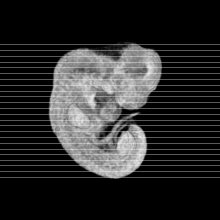

Carnegie Stage 15 (33 post-ovulatory days)

Most embryos at stage 15 are approximately 33 postovulatory days old and measure 7-9 mm in length. Distinguishing criteria for this stage include the appearance of nasal pits and hand plates. The lens vesicles are closed.